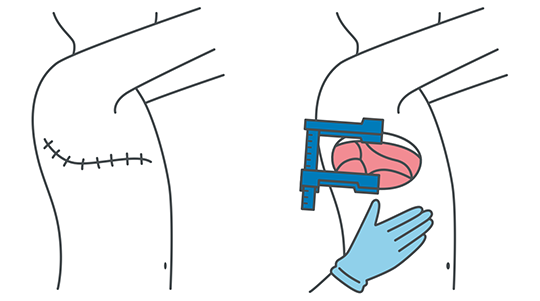

開胸手術と胸腔鏡手術

開胸手術:身体のどこから切るの?

手術を勧められたときに、皮膚をどのように切るのか気にされる方が多いようです。

通常では背中側、肩甲骨の内側から肋骨に沿って斜め下、前の方向に切開します。

肋骨は切り取ってしまうのではなく、押し広げるようにします。